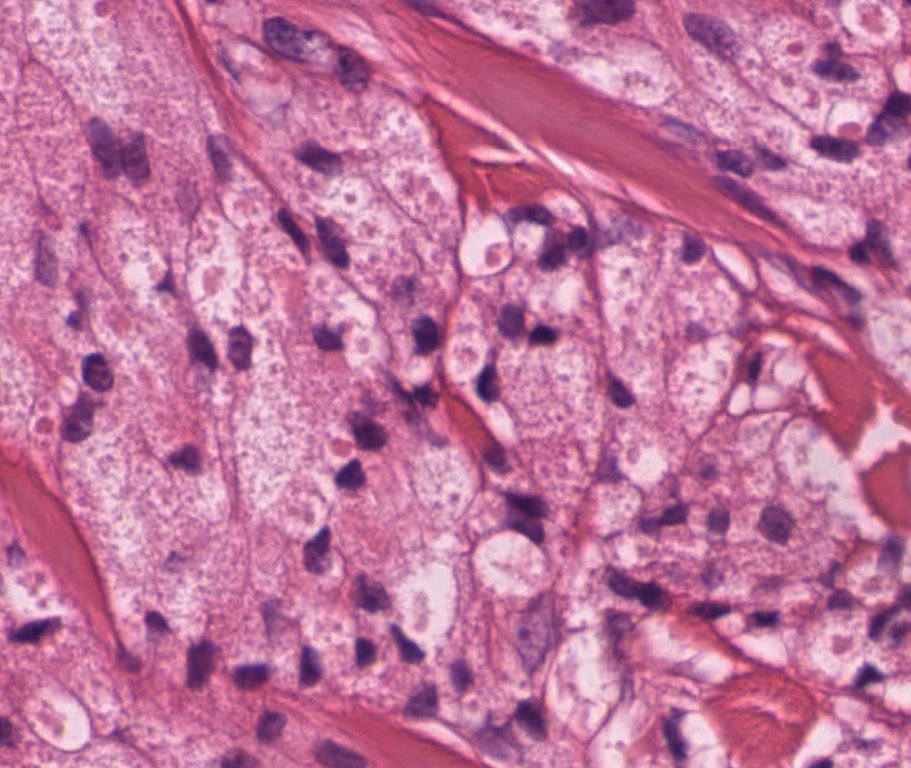

#caseoftheweek What was causing a headache in this 81 year old? #neuropathology #pathX View the whole slide and thousands of others here virtualpathology.leeds.ac.uk/slides/library… on the Leeds virtual pathology website

#caseoftheweek What was causing a headache in this 81 year old? #neuropathology #pathX

View the whole slide and thousands of others here virtualpathology.leeds.ac.uk/slides/library… on the Leeds virtual pathology website